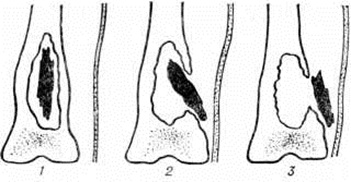

Процесс постепенной секвестрации в ближайшие недели, иногда месяцы, завершается полным отделением некротизированных участков (секвестров) от здоровой костной ткани и образованием костной полости. Величина и форма секвестров может быть различной. При всем их многообразии выделяют следующие виды секвестров: кортикальный (корковый) — при некротизации тонкой костной пластинки под надкостницей; центральный — при омертвении эндостальной поверхности кости; проникающий — при некрозе всей толщи компактного слоя на ограниченном по окружности участке кости; тотальный — при некротизации трубчатой кости по всей её окружности, иногда на протяжении всей кости; циркулярный (венечный) — при некрозе диафиза по всей окружности, но на небольшом участке по длине (секвестр в виде узкого кольца); губчатый — при омертвении спонгиозной ткани длинных трубчатых или плоских костей.

Чаще всего встречаются центральные, кортикальные и проникающие секвестры (рисунок 10). Секвестр может целиком или частично находиться в костной полости или полностью располагаться вне её, в мягких тканях (рисунок 11).

Рентгенологические распознавание секвестров далеко не всегда просто. Иногда секвестр на фоне резко склерозированной окружающей кости вовсе не определяется. Диагностика упрощается, если секвестр отделен от остальной кости грануляционной тканью, выглядящей на рентгенограмме как зона просветления вокруг него (рисунок 14), или когда секвестр частично или полностью отторгся от кости и вышел за пределы костной полости.